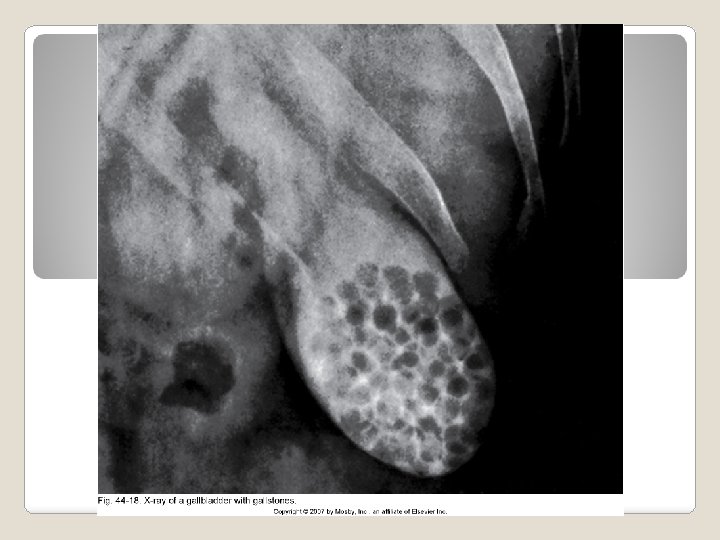

Ultrasound CBC Serum bilirubin (will be elevated) ERCP alkaline phos, ALT, AST, and amylase if the pancreas is involved Elevated Diagnostic Studies